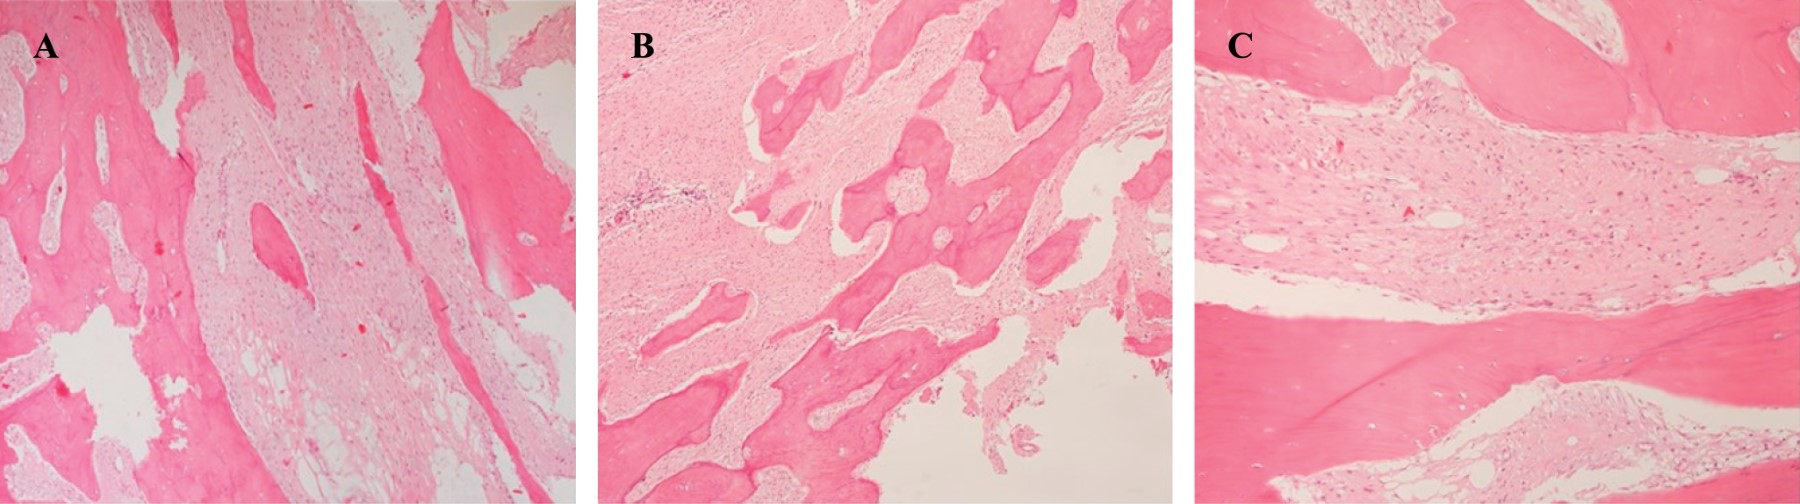

Introducción: el osteosarcoma parosteal convencional es un tumor óseo maligno poco común, que comprende el 4% de todos los osteosarcomas. Aunque es poco común, el osteosarcoma parosteal es el tipo más común de osteosarcoma de la superficie ósea. Presentamos las características clínicas, histológicas y de imagen de una variante histológica rara de un osteosarcoma parosteal, revisamos la literatura y enfatizamos la importancia de la correlación radio-patológica, así como la interpretación de una biopsia representativa para obtener el diagnóstico correcto. Reporte de caso: mujer de 36 años inició su cuadro un año antes de su ingreso al hospital con aumento de volumen en rodilla izquierda y dolor. Los estudios de imagen mostraron una tumoración heterogénea yuxtacortical localizada en la superficie posterior de la metáfisis femoral distal. Se realizó biopsia incisional, con diagnóstico de osteosarcoma parosteal y se realizó resección quirúrgica amplia. De acuerdo con los hallazgos de la pieza quirúrgica se realizó el diagnóstico de osteosarcoma parosteal con componentes de condrosarcoma y liposarcoma de bajo grado. El conocimiento de esta rara variante de osteosarcoma parosteal puede llevar a los ortopedistas oncólogos a considerar otros componentes y proporcionar márgenes quirúrgicos adecuados. Conclusión: presentamos las características clínicas, histológicas y de imagen de un osteosarcoma parosteal con componentes de liposarcoma y condrosarcoma de bajo grado.

Figura 2